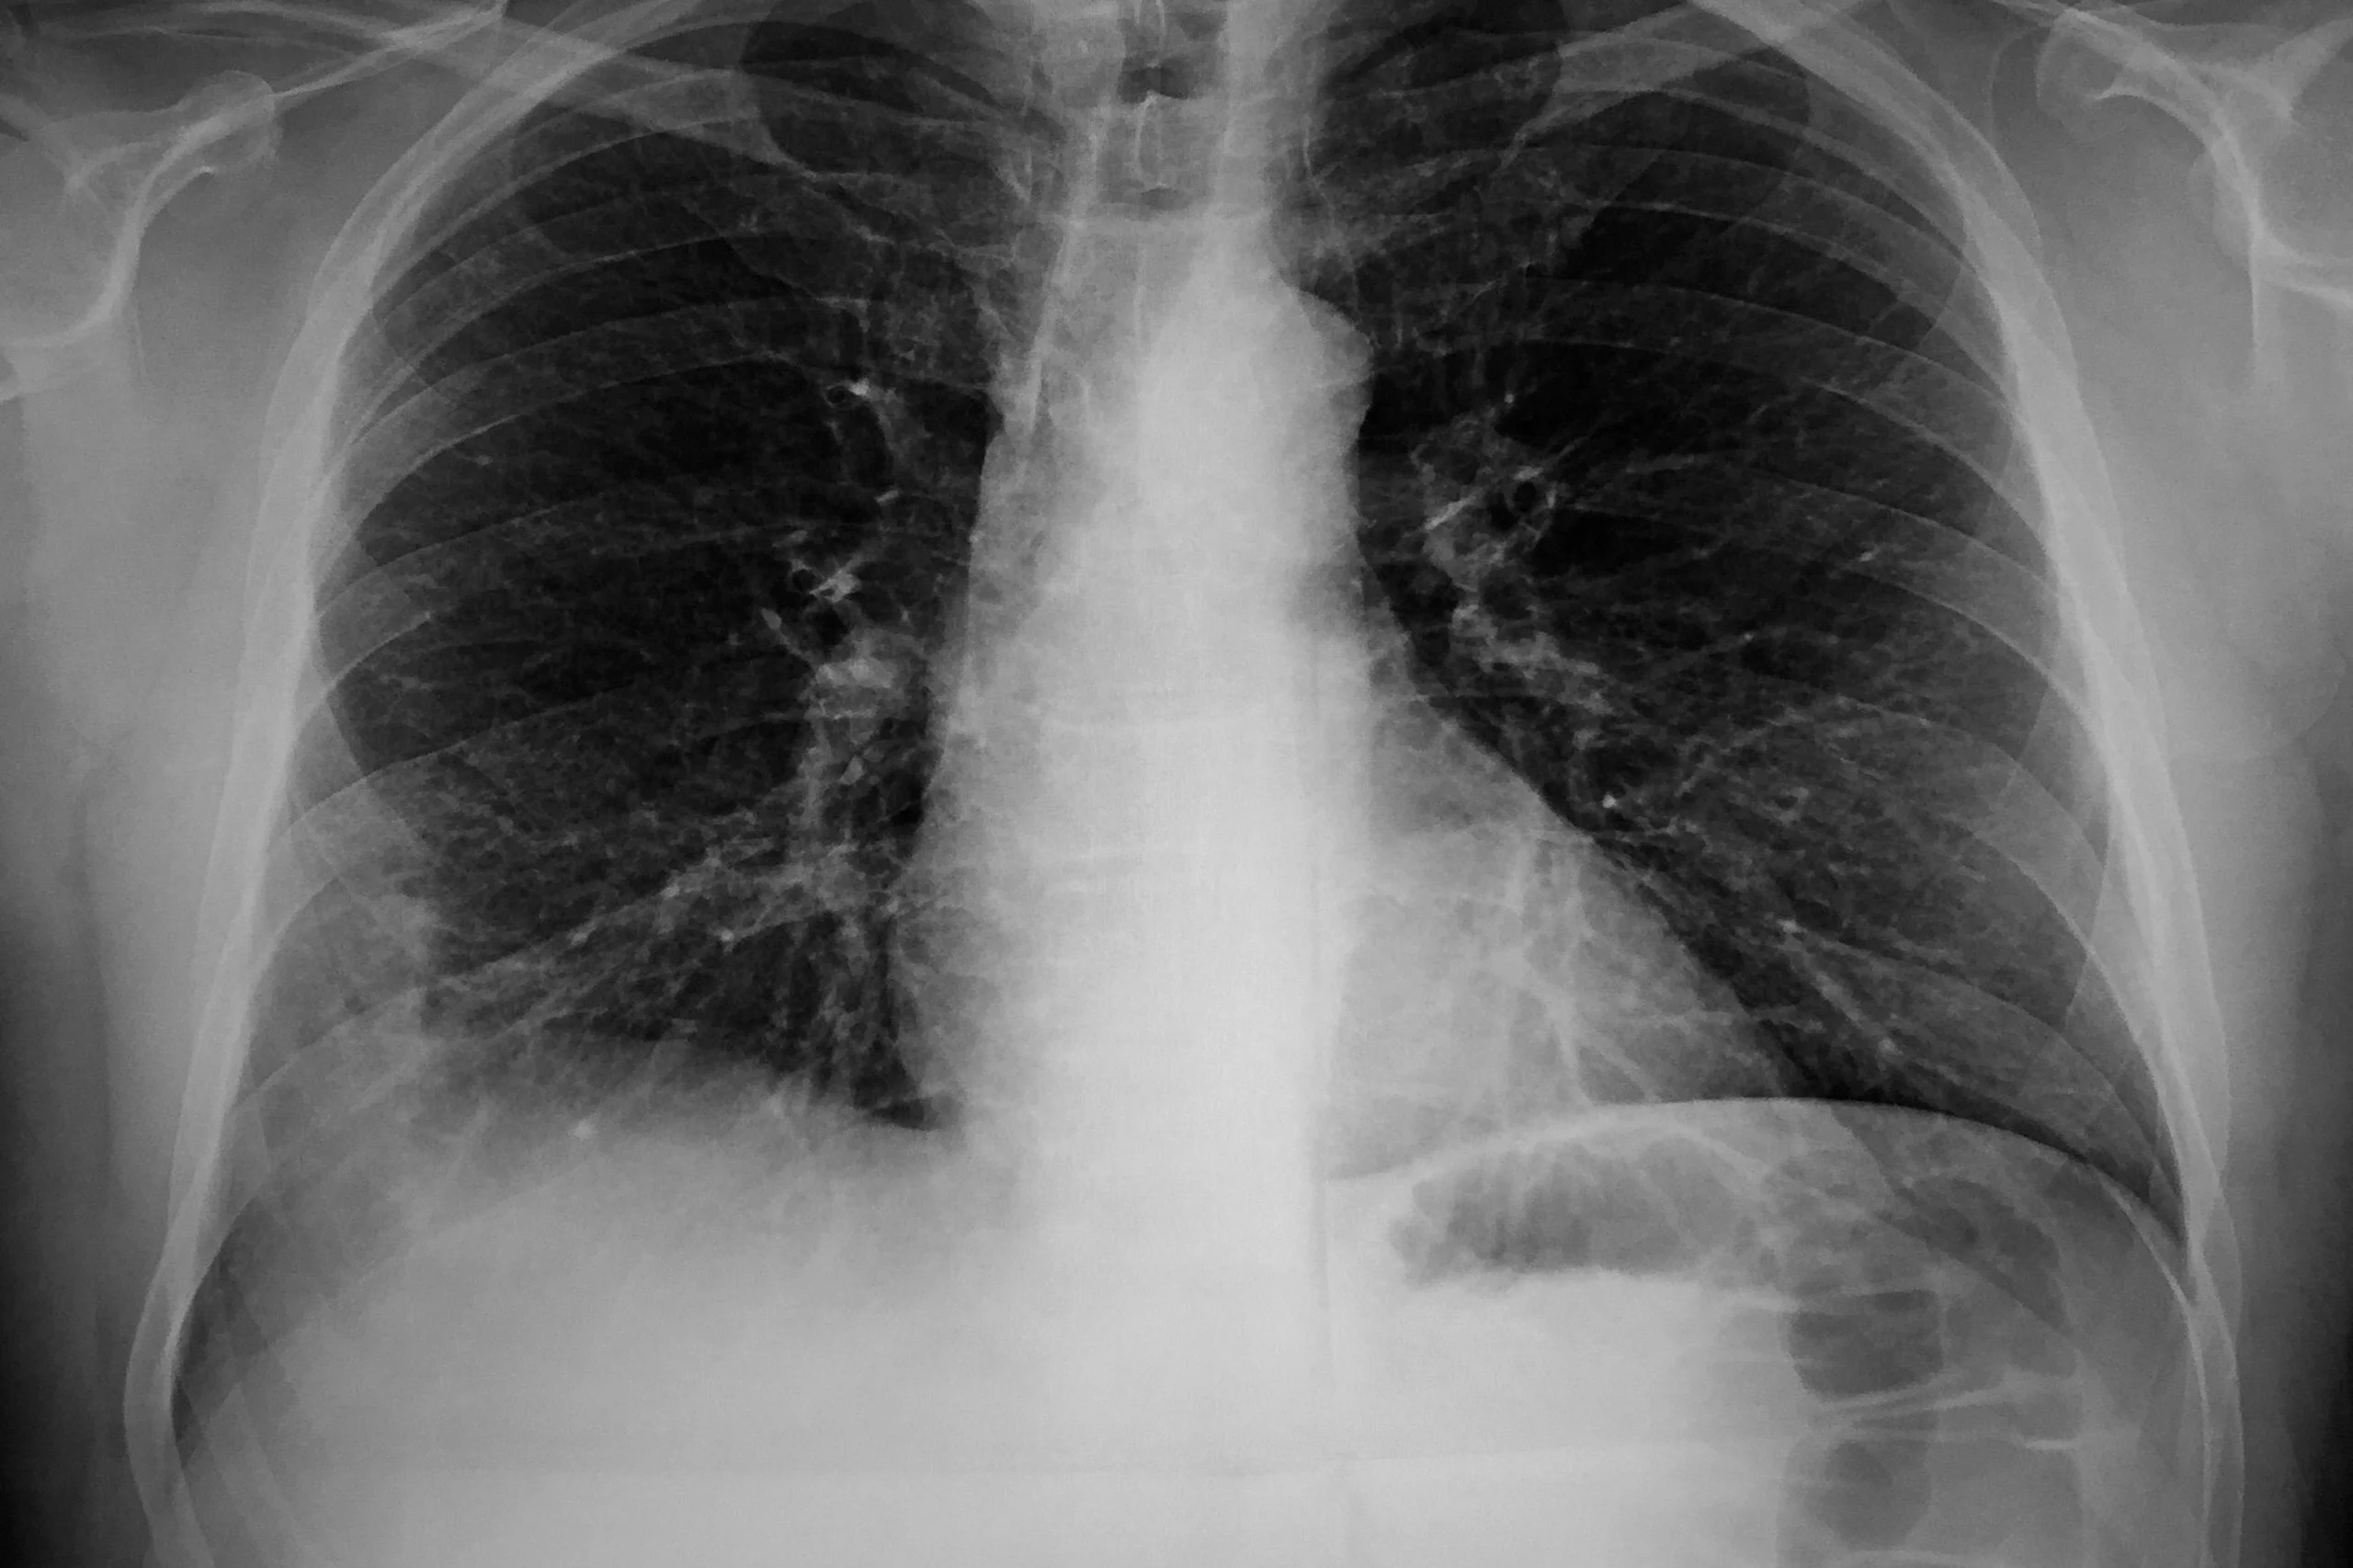

При подозрении на наличие микоплазменной пневмонии назначается рентген. Лечение проходит амбулаторно, госпитализация ребенка требуется в исключительных случаях. Обычно назначают антибиотики группы макролидов.